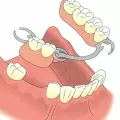

- Съемное (коронки, в т.ч. частичные, мостовидные, пластиночные и бюгельные протезы).

В статьях данной категории мы расскажем о методах фиксации на челюсти, правилах ухода, о любимых ортопедами материалах и способах установки